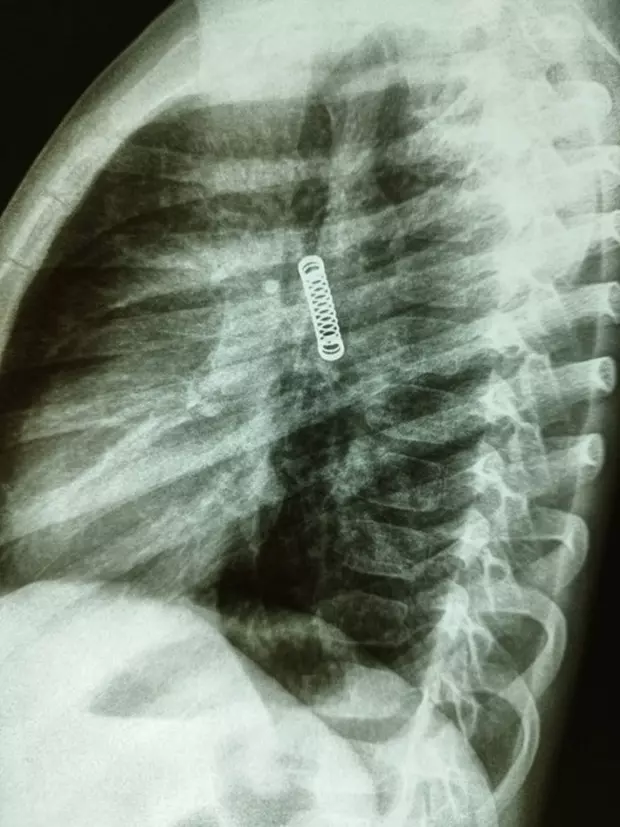

În timp ce efectuau verificări ample pentru a detecta problema, medicii au fost uimiți să găsească un obiect metalic, mai exact arcul unui pix, în plămânul stâng al copilului. Obiectul a fost vizibil pe radiografie.

Copilul este acum într-o stare stabilă, după ce medicii au îndepărtat cu succes arcul, pe 8 martie.

Dr. Carlos Morinigo a spus că procedura a fost complicată din cauza timpului în care obiectul străin a stat în plămânul băiatului și a daunelor pe care le-a provocat.

Cu toate acestea, în ciuda faptului că obiectul a dus la o „scădere probabilă' a capacității plămânilor, doctorul Morinigo a precizat că starea plămânilor se va îmbunătăți pe măsură ce băiatul va crește. Medicul a postat pe rețelele de socializare câteva fotografii cu arcul de pix din plămânul băiatului.